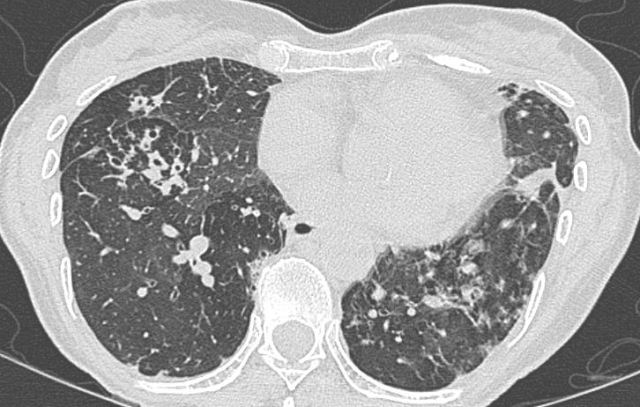

The setting – patients with bronchiectasis (including those with cystic fibrosis) have impaired respiratory secretion clearance and a vastly different lower respiratory flora (microbiome) than patients with normal lungs. They are frequently colonised with conventional respiratory species such as Haemophilus influenzae and Moraxella catarrhalis, Staphylococcus aureus, a diverse range of Gram negative bacteria and even fungi. Colonisation/infection with non-tuberculous […]